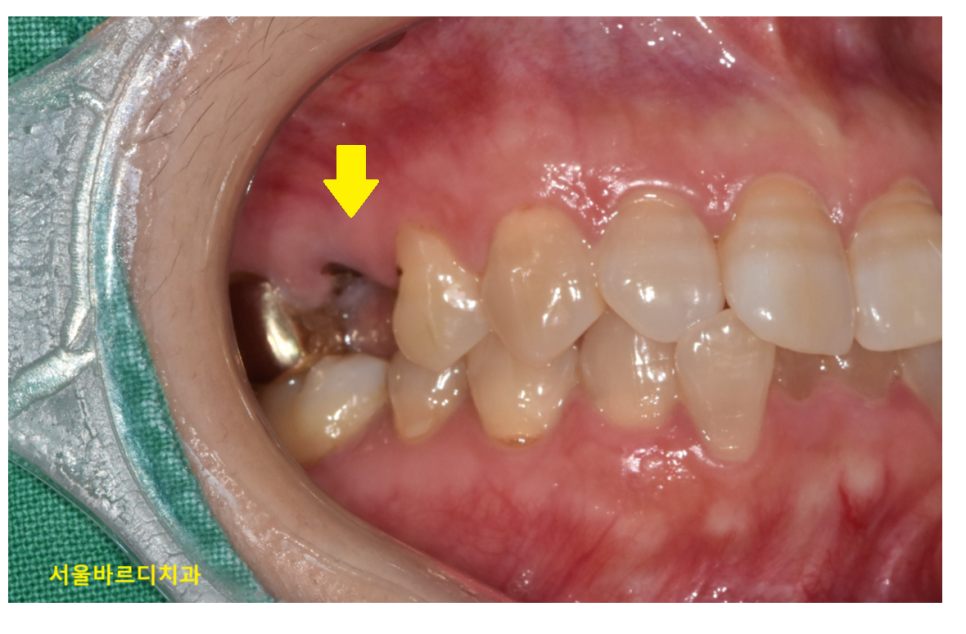

치관 부위

내 치아가 일부 남아있으면

살려볼 수 있었겠지만

발치 후 임플란트가 대안이 되겠습니다.